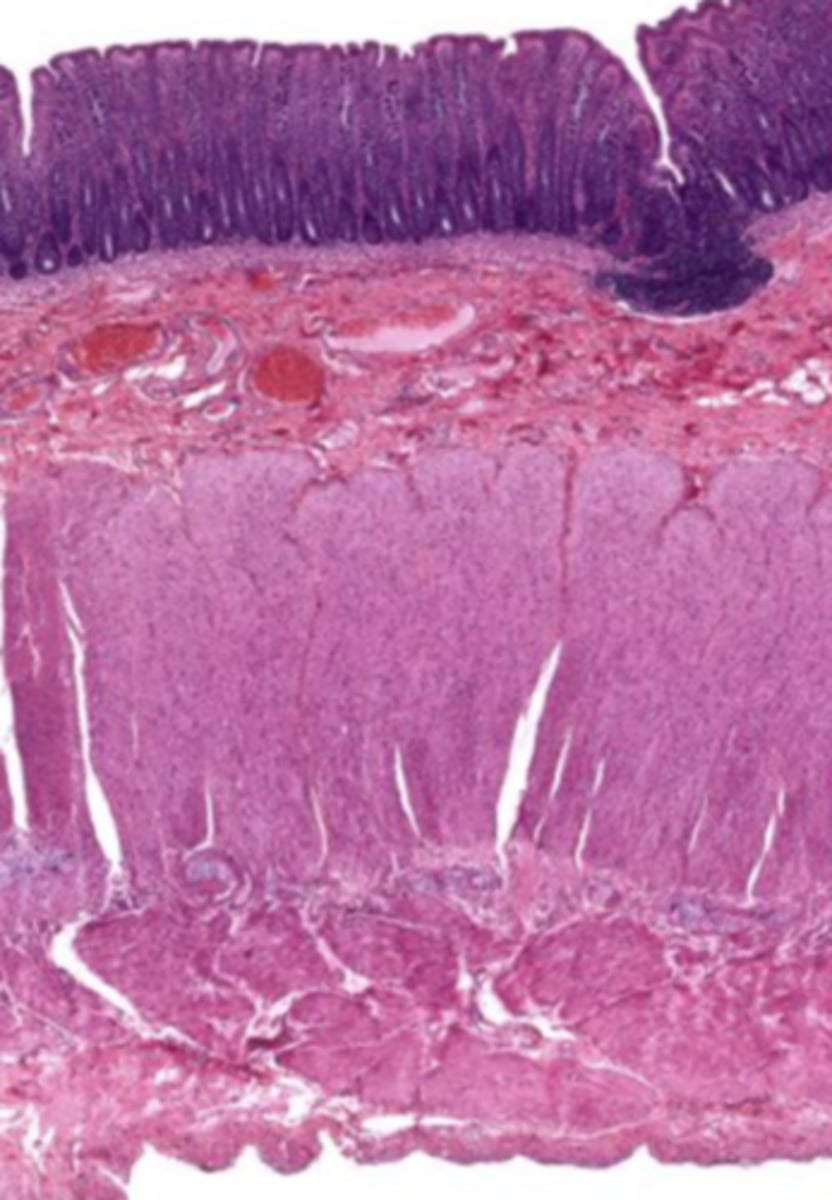

cardiac stomach (histology)

simple columnar epithelium

what kind of epithelium lines the mucosa of the cardiac stomach?

gastric pit (cardiac stomach)

lumen (cardiac stomach)

mucosa (cardiac stomach)

mucosal epithelium (cardiac stomach)

lamina propria (cardiac stomach)

muscularis mucosa (cardiac stomach)

submucosa (cardiac stomach)

contains glands and blood supply

muscularis externa (cardiac stomach)

serosa/adventitia (cardiac stomach)